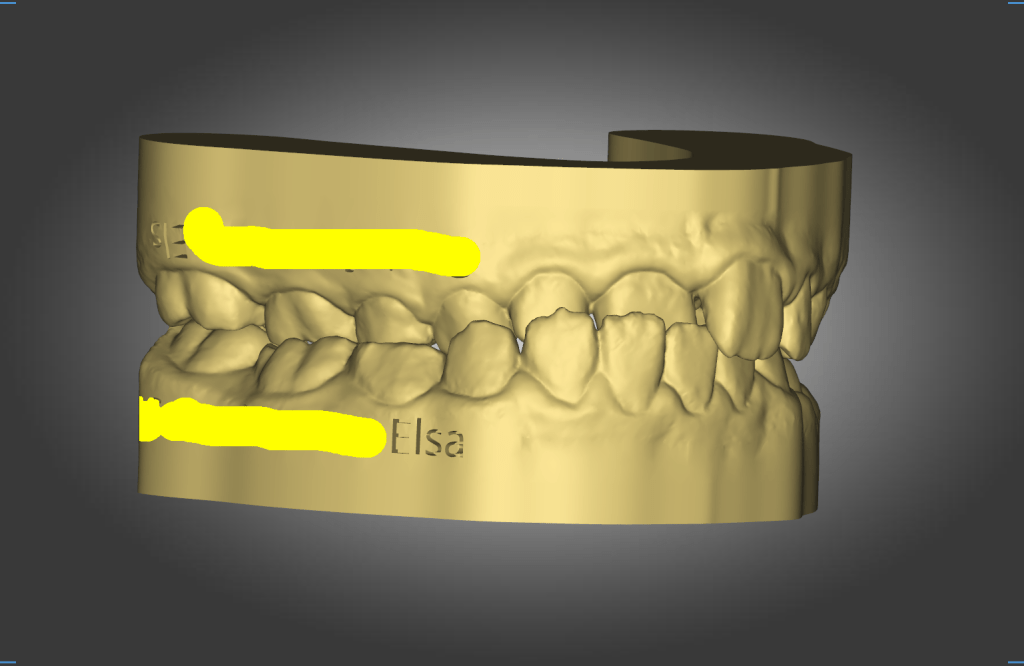

Elsa,G-H – Myofunctional Therapy (MFT)

Unilateral Hemi Sectional Cross Bite, Mixed Dentition – Female 10 yo Read.